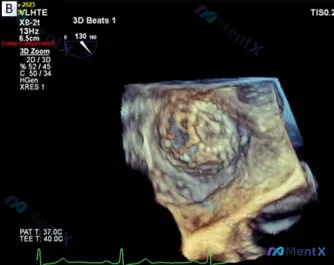

网上看到一份病例资料: WATCHMAN左心耳封堵术后2周的TEE随访,3D重建图像显示二尖瓣后叶(看起来像P2/P3区)向左心房侧明显膨出,瓣缘好像还有点不连续,符合连枷样运动的表现。 术前的基线资料暂时没放,但术后2周这个时间点很关键。 大家第一眼看到这个TEE表现,思路会怎么分?是先考虑退行性...